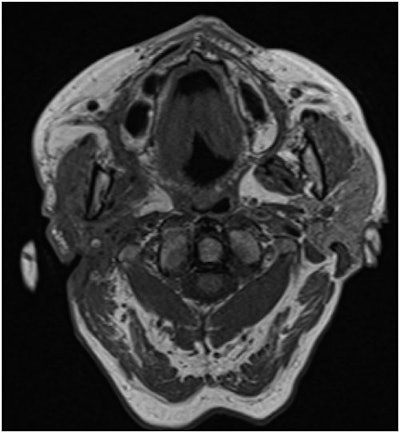

The woman underwent a CT scan that showed a swollen right parotid gland in the parapharyngeal space expanding toward the cutis and the palatine tonsil, with tapering of the internal carotid artery and the presence of subcutaneous infiltration, which suggested a deep parotid abscess, they wrote.

Two months after treatment, an MRI scan showed volume loss of her parotid gland and no signs of malignancy. Six months after treatment, the woman's facial nerve still had not improved. The patient was scheduled to undergo implantation of a gold-weighted implant in her upper eyelid to treat her persistent open eye caused by facial nerve paralysis.